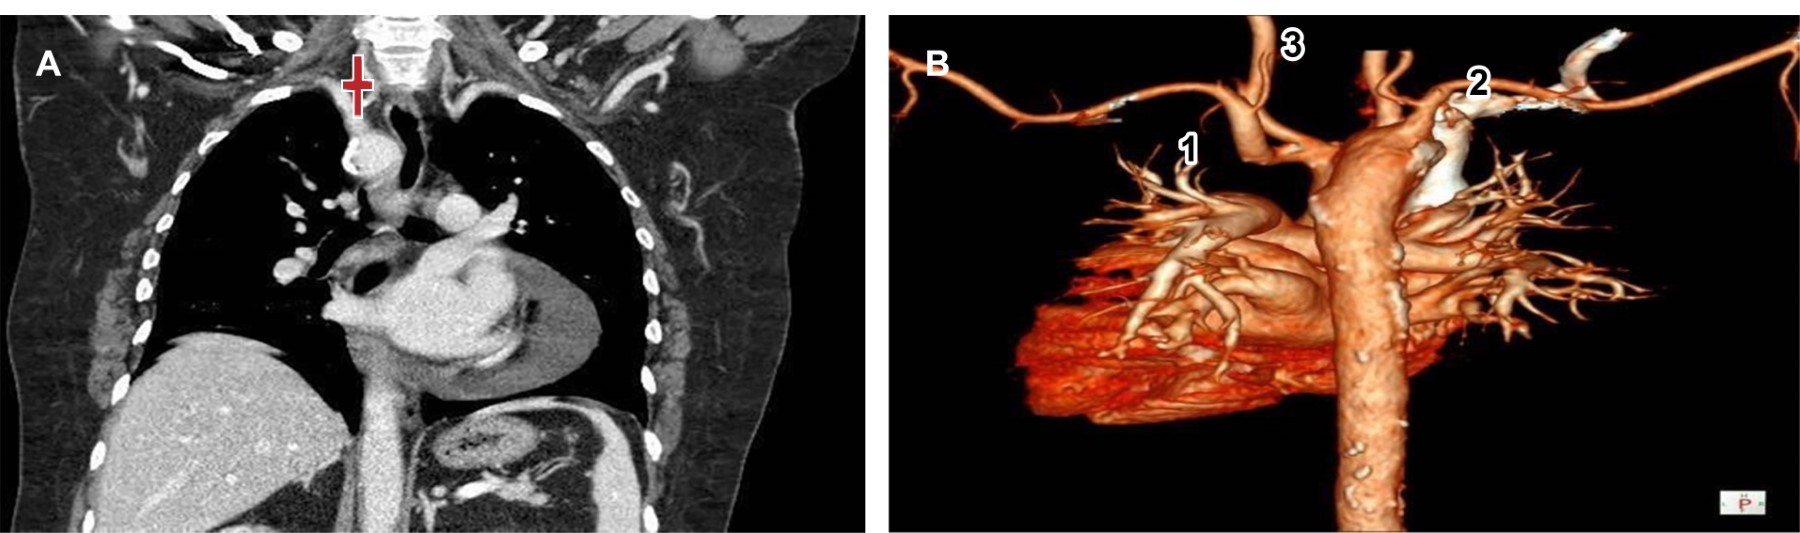

Paciente femenino de 64 años de edad a la que se le solicitó tomografía de tórax en alta resolución por parte del Servicio de Neumología debido a infecciones de vías respiratorias superiores recurrentes; sin embargo, como hallazgo, se visualizó arco aórtico derecho (Figura 1) con patrón de ramificación en espejo (arteria subclavia derecha y arteria carótida común derechos que se originan directamente del cayado aórtico y tronco braquiocefálico izquierdo) (Figura 2).

El tipo I o con patrón de ramificación en espejo es la variación en este caso y representa la categoría más frecuente, consiste en la presencia de un tronco braquiocefálico del lado izquierdo de donde emergen la arteria carótida común y subclavia izquierdas, además de arteria carótida común y subclavia derechas que emergen directamente del arco aórtico y no del tronco braquiocefálico (Figura 2) como ocurre en condiciones normales.1

Figura 1

Figura 2